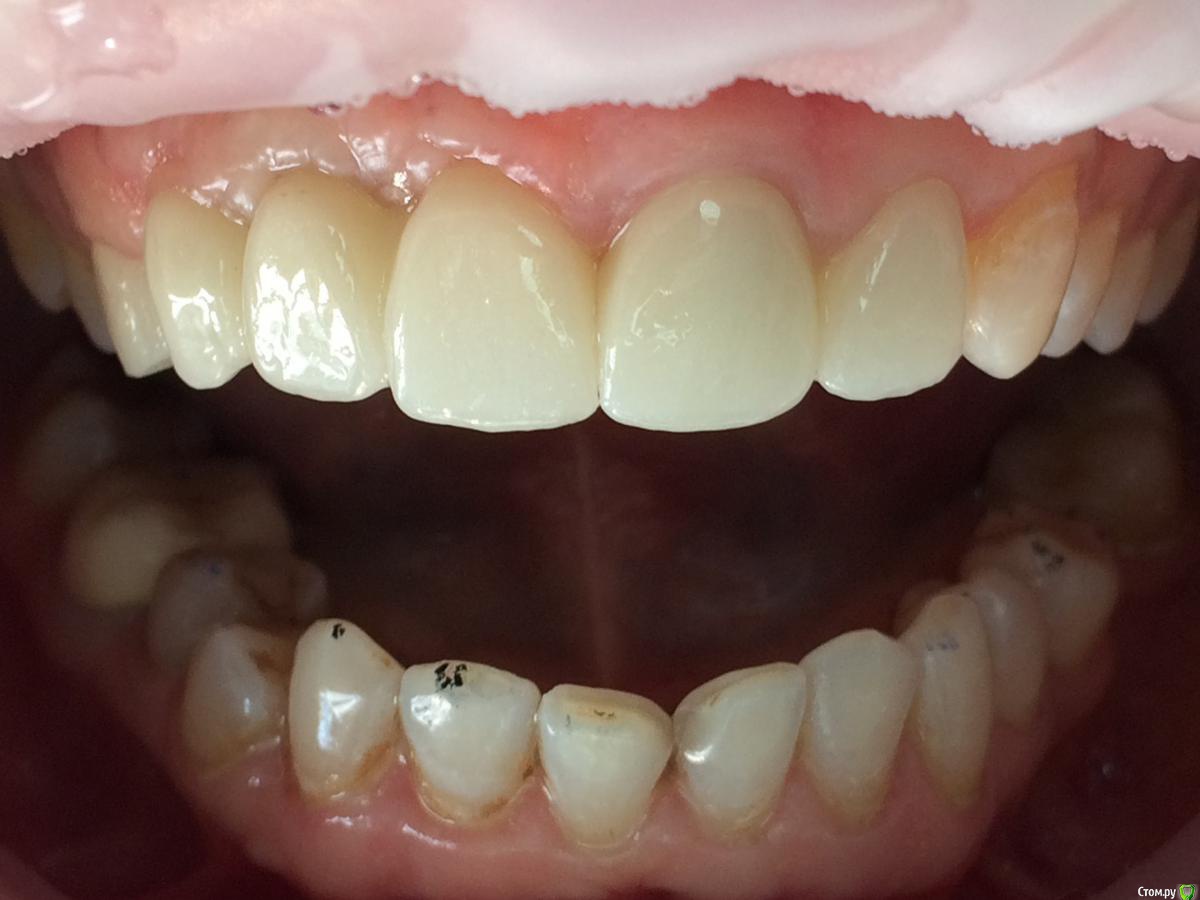

kamranchick Опубликовано 11 апреля, 2019 Автор Поделиться Опубликовано 11 апреля, 2019 Рекол 6 месяцев Ссылка на комментарий